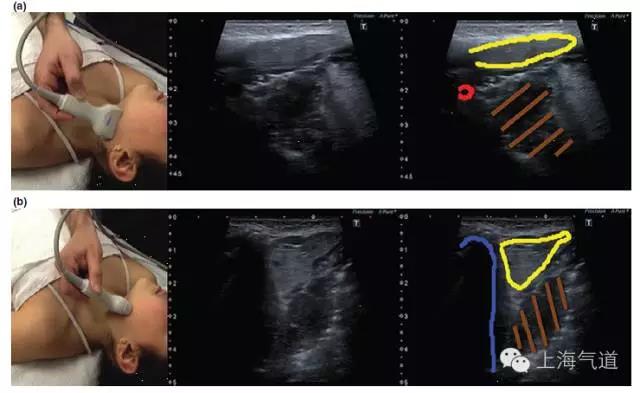

图2a. 将探头置于颏下区取横断面,绿色区域为舌体,红色为口腔内肌肉组织,蓝色为下颌骨及其伪影。b.将探头旋转90度并置于中线位置,取此区域的长轴影像

图3 a. 探头置于下颌骨水平取纵断面,黄色为颌下腺,红色为颈外动脉,棕色为扁桃体。b. 将探头旋转90度所得此区域的影像